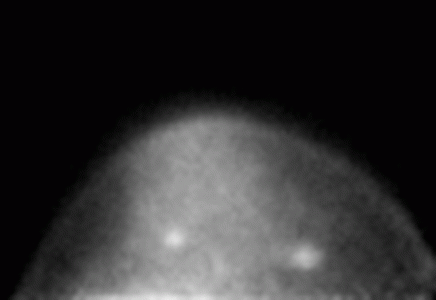

This PEM image shows two cancerous lesions. The one on the right was depicted by conventional mammography, but the one on the left was only identified by the PEM unit. Image courtesy: Eric Rosen, Duke University Medical Center

Dedicated positron emission mammography (PEM) systems potentially provide a high sensitivity, high resolution alternative to whole body PET for positron breast imaging. In collaboration with Duke University Medical Center (Tim Turkington, PI), we have designed, built and evaluated a large field of view (15 cm x 20 cm) PEM system. The device is built with a set of two pixellated LGSO/LYSO crystal scintillators coupled to arrays of compact position sensitive photomultiplier tubes. In pre-clinical trials performed at Duke lesions as small as 4 mm were seen in phantom experiments using advanced iterative image reconstruction algorithms developed at Jefferson Lab. Subsequent clinical trials at Duke supported by the DoD (Eric Rosen, PI) showed that small primary breast malignancies can be imaged. An NIH-funded clinical study at Duke is underway to scan 200 patients with suspected breast cancer (Mary Scott Soo, PI).